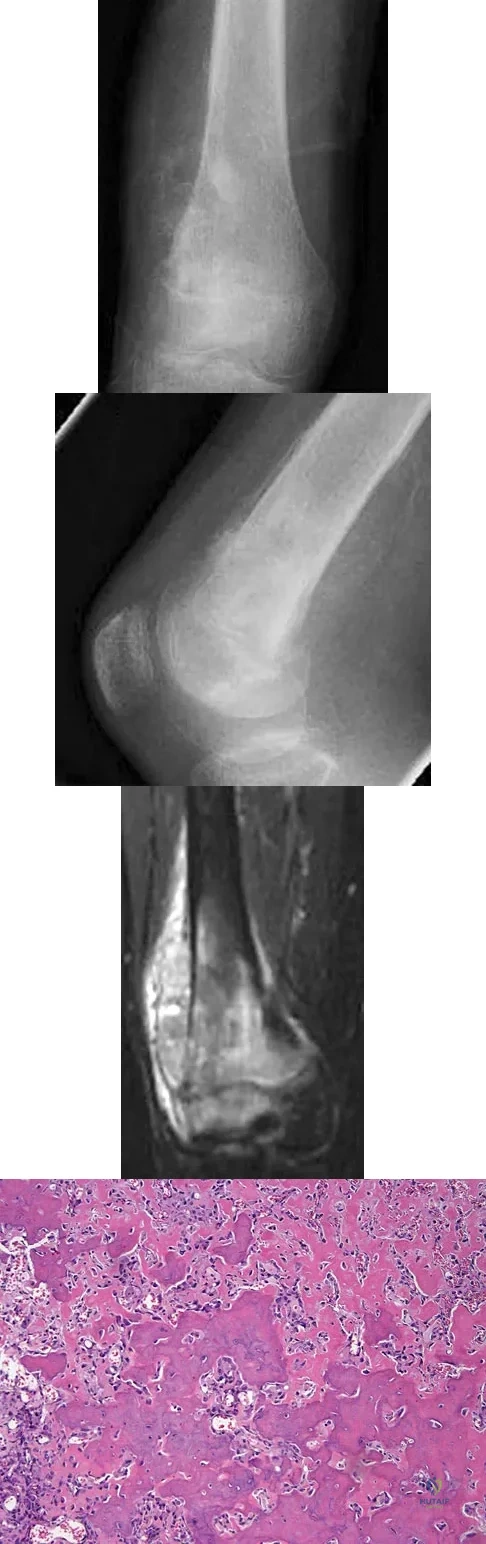

A healthy 16-year-old boy has had increasing pain in the right knee for the past 3 months. Examination reveals warmth and swelling around the distal femur. Radiographs and an MRI scan are shown in Figures 51a through 51c, and a biopsy specimen is shown in Figure 51d. What is the most likely diagnosis?

Explanation